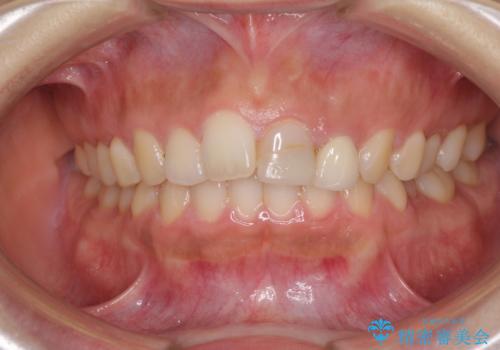

- 中学生の時にスポーツで折ってしまった前歯が変色してしまったとのことで来院された患者様です。

結婚式に向けてオールセラミッククラウンにて仕上げていくこととしました。

既にクラウンが装着されていた歯は歯根の先端に病変が認められたため、根管治療を行うこととしました。

仮歯装着の時点で自然な見た目となり、オールセラミッククラウンを装着した際には、まるで自分の歯のようと喜んでくださいました。